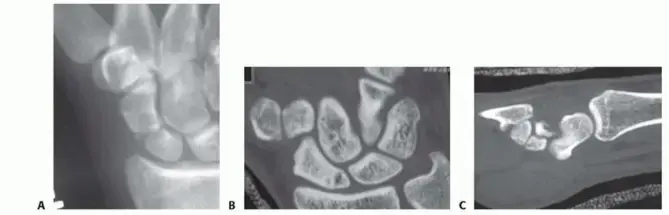

متى يجب عليك زيارة الطبيب؟

يوصي الأستاذ الدكتور محمد هطيف بضرورة زيارة طبيب متخصص في جراحة العظام في أسرع وقت ممكن إذا تعرضت لأي إصابة في الرسغ، خاصة إذا كنت قد سقطت على يد ممدودة، وظهرت لديك أي من الأعراض المذكورة أعلاه، حتى لو كان الألم خفيفًا. التشخيص المبكر عن طريق الأشعة السينية، أو في بعض الحالات، الرنين المغناطيسي (MRI) أو التصوير المقطعي (CT)، هو الخطوة الأولى والأكثر أهمية لتحديد خطة العلاج المناسبة وتجنب المضاعفات طويلة الأمد التي قد تؤثر سلبًا على جودة حياتك.